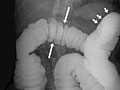

A barium enema is an X-ray exam of the large intestine (colon and rectum). It may also be called a lower gastrointestinal (GI) exam. The test is used to help find diseases and other problems that affect the large intestine. The colon is filled with a contrast material that contains barium so that the intestine can be seen on an X-ray. This is done by pouring the contrast material through a tube inserted into the anus. The barium blocks X-rays. This causes the barium-filled colon to show up clearly on the X-ray picture.

• In a single-contrast study, the colon is filled with barium. This outlines the intestine and shows large abnormalities.

• In a double-contrast or air-contrast study, the colon is first filled with barium, and then the barium is drained out. This leaves only a thin layer of barium on the wall of the colon. The colon is then filled with air. This provides a detailed view of the inner surface of the colon. It makes it easier to see narrowed areas (strictures), diverticula, and swelling.